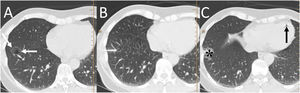

Spontaneous PTX has been described in 0.03%−0.05% of patients with primary lung neoplasia (Fig. 11), with a clear predominance of males (90%).28 Presentation of pulmonary neoplasia as spontaneous PTX appears in patients with advanced disease.28 An underlying lung neoplasm should be ruled out in patients under 40 years of age with recurrent pneumothorax, or in patients over 40 years with a history of smoking, chronic bronchitis or emphysema, with incomplete lung expansion or a lung mass on chest radiograph after pleural drainage.28

A 57-year-old man with a disseminated lung neoplasm undergoing chemotherapy. A) The chest X-ray revealed a right lung mass with left lung nodules (white arrows) and an air-fluid level in the right hemithorax due to hydropneumothorax (black arrows). B) The computed tomography scan revealed a large right lung mass (black asterisk), lung nodules and masses and contralateral hilar adenopathies (white arrows), and the right hydropneumothorax (black arrow). The patient died within a few days.

Bilateral spontaneous PTX, which represents 1.3% of spontaneous PTX, has also been described as a complication of a unilateral transthoracic puncture29 (Fig. 12).

A 72-year-old man with a pulmonary nodule in the right upper lobe. Percutaneous fine needle (22 G) lung puncture cytology was of a non-small cell lung neoplasm. A and B) The chest X-ray 72 h after the procedure revealed signs of pneumomediastinum and significant subcutaneous emphysema (white arrows). The biopsied pulmonary nodule can be seen in the periphery of the right upper lobe in the posteroanterior view of the chest X-ray (black arrows). B and C) Computed tomography confirmed pneumomediastinum and subcutaneous emphysema and showed predominantly left bilateral pneumothorax (white arrows) with communication between both pleural spaces in the anterior junctional line (black arrows), probably of congenital origin, since there was no previous thoracic surgery. The subcutaneous emphysema was drained through an incision in the chest wall and multiple pleural adhesions were identified during the surgical procedure of right upper lobectomy.

It must be remembered that: exceptionally, there is communication between the two pleural spaces in the anterior junctional line, which results in a single pleural space. This may be secondary to previous surgery with median sternotomy ("iatrogenic buffalo chest'') or a communication of congenital origin.29,30